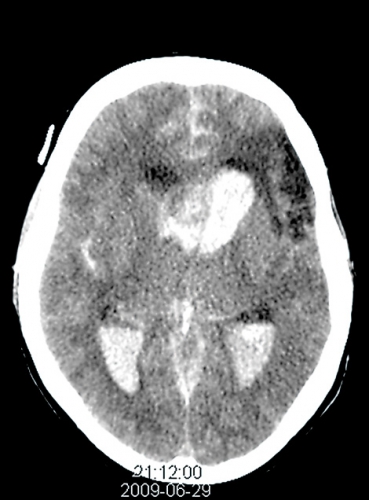

Nästa dag genomfördes framgångsrikt endovaskulär embolisering (coiling) av aneurysmet. I samband med behandlingen uppstod en embolisering till en större arteria cerebri media-gren, vilken inte kunde lösas med vare sig trombolys eller trombektomi. Under ingreppet fick patienten en 15 sekunders asystoli, som behandlades med atropin. Försämrad intrakraniell tryckmätarkurva med tecken på ett högre ICP föranledde förnyad datortomografi, vilken visade fortsatt progress av blödningen (Figur 1) och begynnande tecken på ischemi i området som motsvarade den trombotiserade mediagrenen. Beslut fattades att inte vidta ytterligare neurokirurgiska åtgärder. En förnyad medvetandekontroll visade RLS 8, och sederingen återinsattes inte. Under kvällen/natten dilaterades pupillerna maximalt, kroppstemperaturen sjönk och en Cushing-reflex följd av blodtryckssänkning noterades (Figur 2).